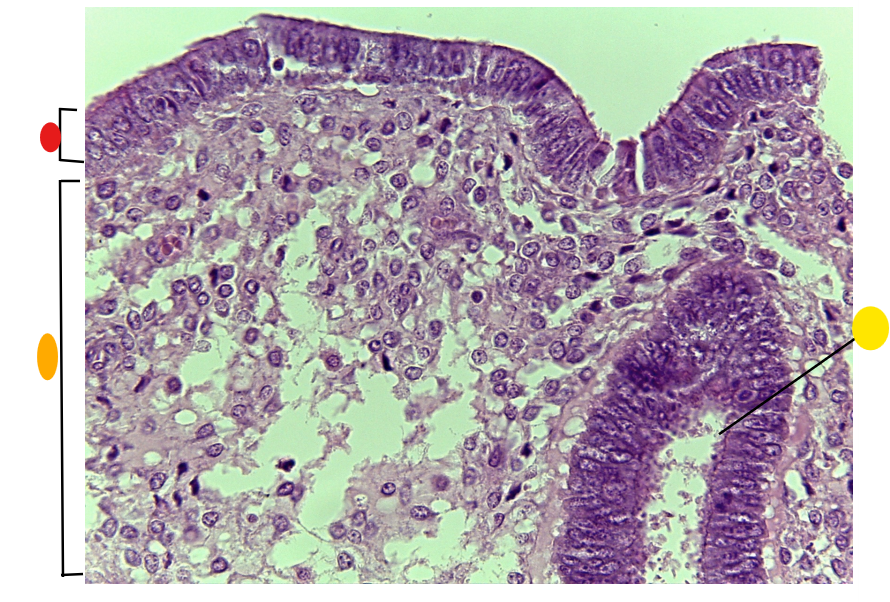

red

granulosa cells

orange

thecal cells

yellow

zona pellucida

What is this

secondary follicle